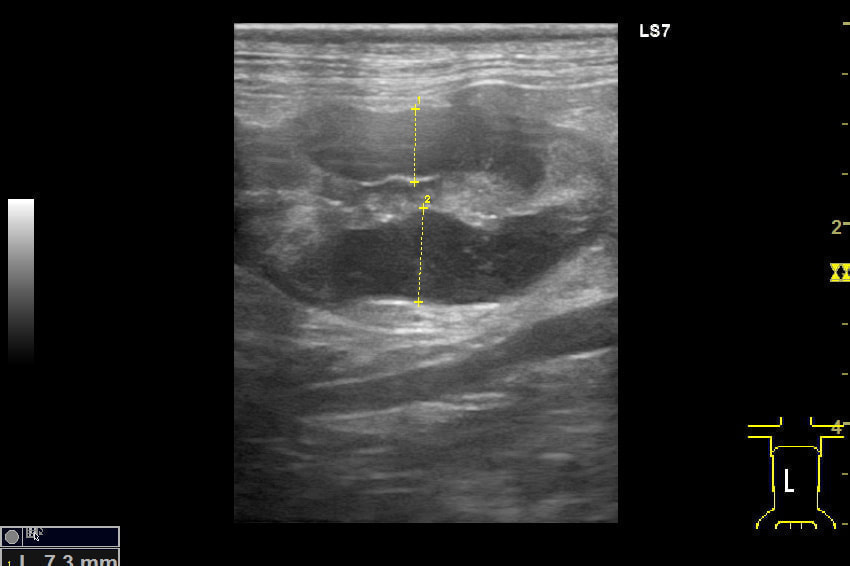

腸のエコー画像

吐き気のあるワンちゃんです。腸の壁が腫れています。